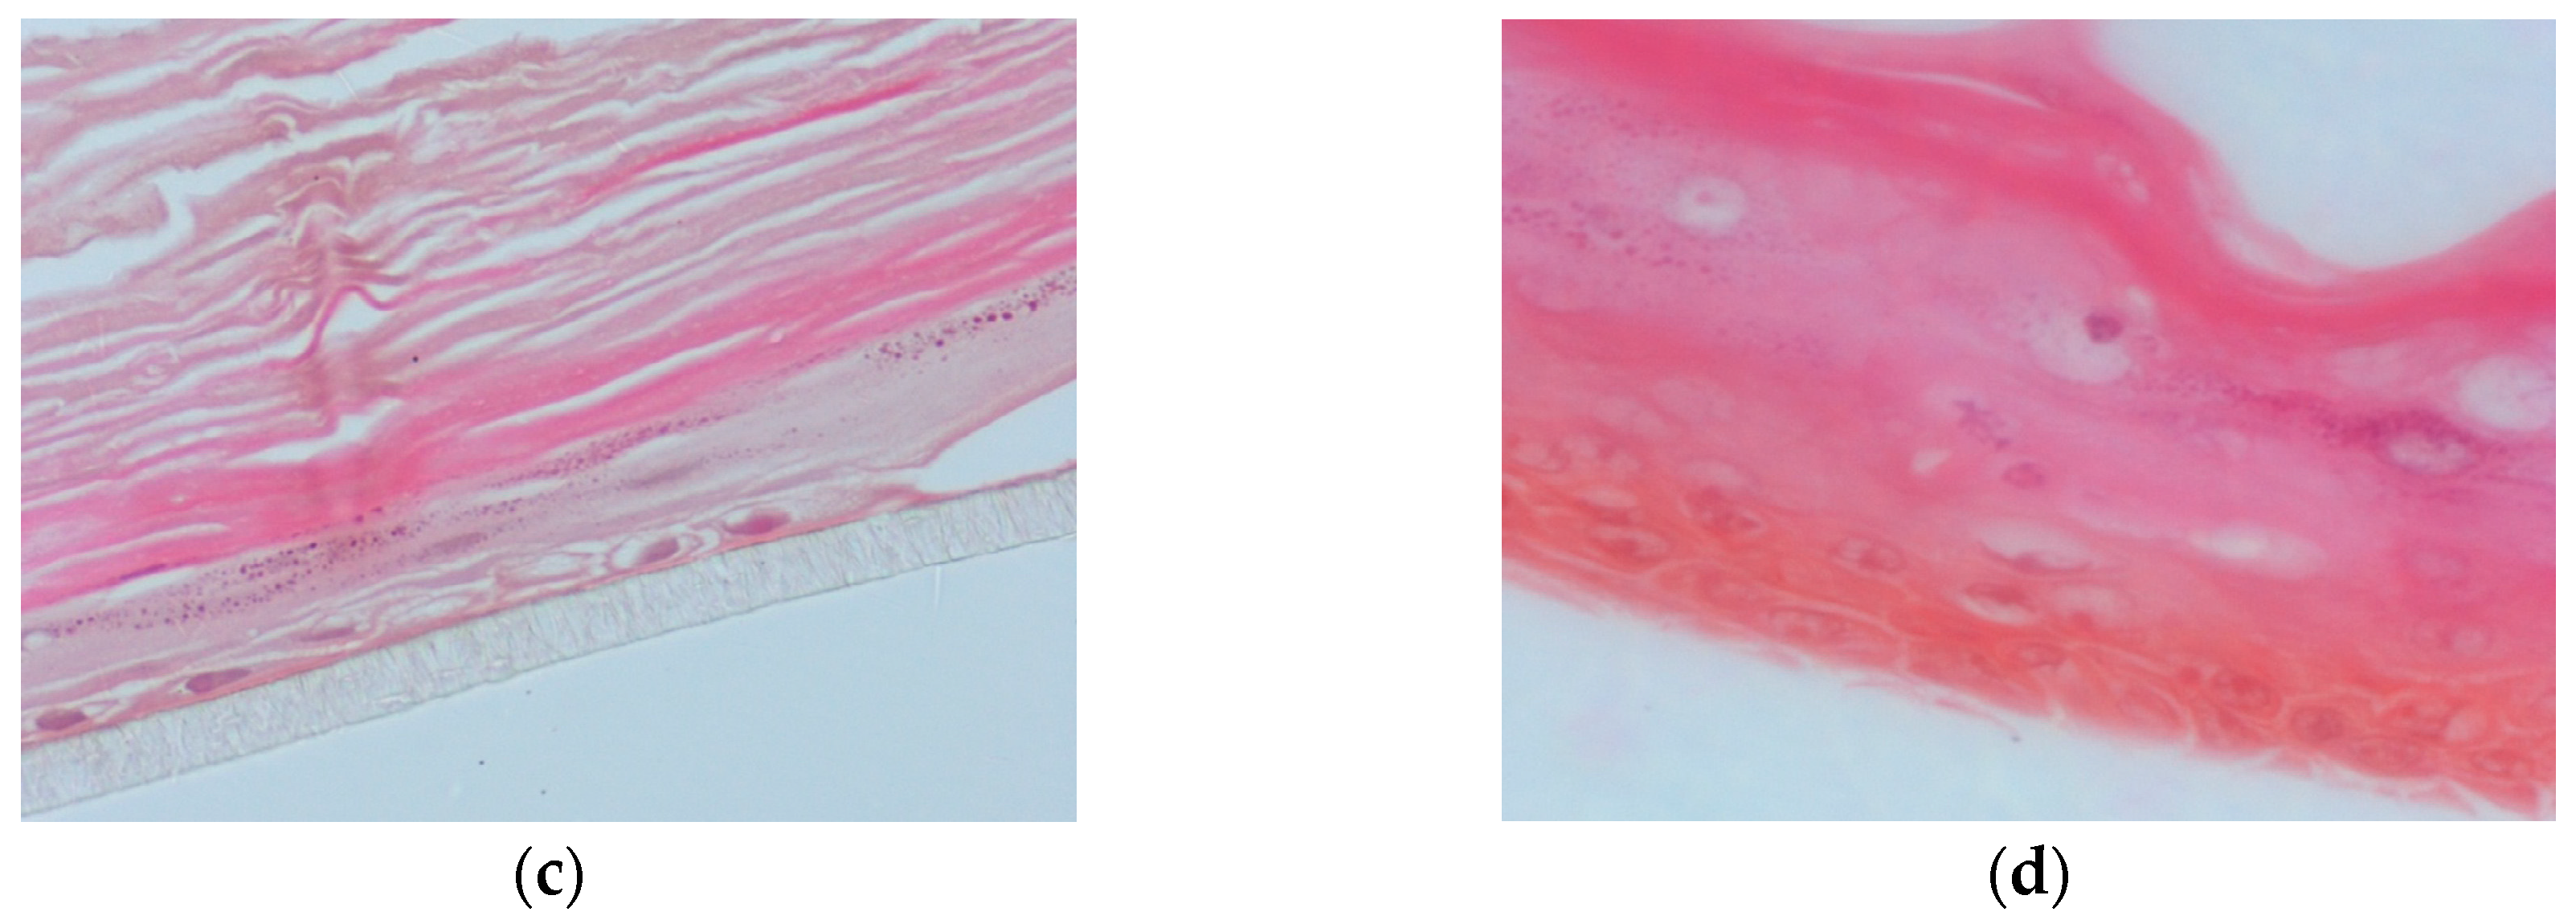

2.11. Human Reconstituted Skin Tissue Model (EpiDermTM EPI-200)

2.12. Treatment and UVB Irradiation of EpiDermTM EPI-200

2.14. Immunohistochemistry (IHC)

3.4. Propolis Extracts Inhibit UVB-Induced Overexpression of Matrix Metalloproteinases (MMPs) in a Human Reconstituted Skin Model